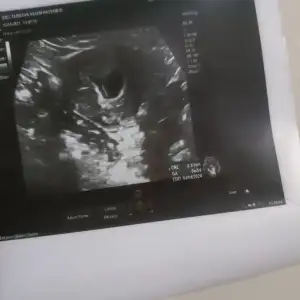

Selamm biz dün kalp artışlarımızı duydukk 6+5 te 🥹🧿

Eklentiler

• IMG_20230815_231140.webp

IMG_20230815_231140.webp

19,6 KB · Görüntüleme: 109